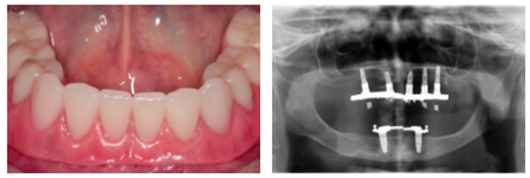

Agora, a macrogeometria com câmaras de cicatrização presentes no corpo dos implantes e o conceito de redução de plataforma (plataforma switching) estão presentes nos hexágonos internos e externos da Implacil De Bortoli. Essas novidades flexibilizam o uso do HE e do HI, que passam a atender todas as situações clínicas, com o benefício de oferecer menor tempo e melhor qualidade na osseointegração.

A macrogeometria exclusiva e inovadora da Linha Maestro, da Implacil De Bortoli, chegou aos hexágonos internos e externos, que agora contam com os benefícios das conexões com plataforma de 3.5 para os implantes de Hexágono Interno Switch 4.0 e 5.0 de diâmetro. Essa vantagem consta também nos implantes de diâmetro 5.0 Hexágono Externo Switch com a plataforma 4.0, padrão HE.

Dessa maneira, foram agregadas as câmaras de cicatrização no corpo do HE Switch e do HI Switch – uma característica do implante Maestro que, comprovadamente, acelera e melhora a qualidade da osseointegração. Além disso, o conceito de redução de plataforma (plataforma switching) entre o pilar e o implante promove menor perda da crista ósseo ao redor dos implantes, mais espaço para a elaboração do perfil de emergência das coroas e facilita a seleção de pilares.

A nova linha é indicada para todas as situações clínicas e, quando inserido até 1 mm infraóssea, apresenta ausência ou redução significante na saucerização ao seu redor, algo que nunca foi possível para implantes HE e HI. Essa macrogeometria possibilita uma osseointegração em menos tempo e com qualidade, sendo possível realizar carga imediata, tardia ou precoce (com dois meses).